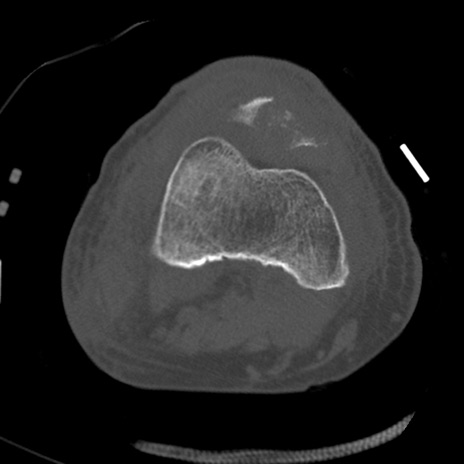

症例28 右膝関節CT(横断像)

右膝関節CT